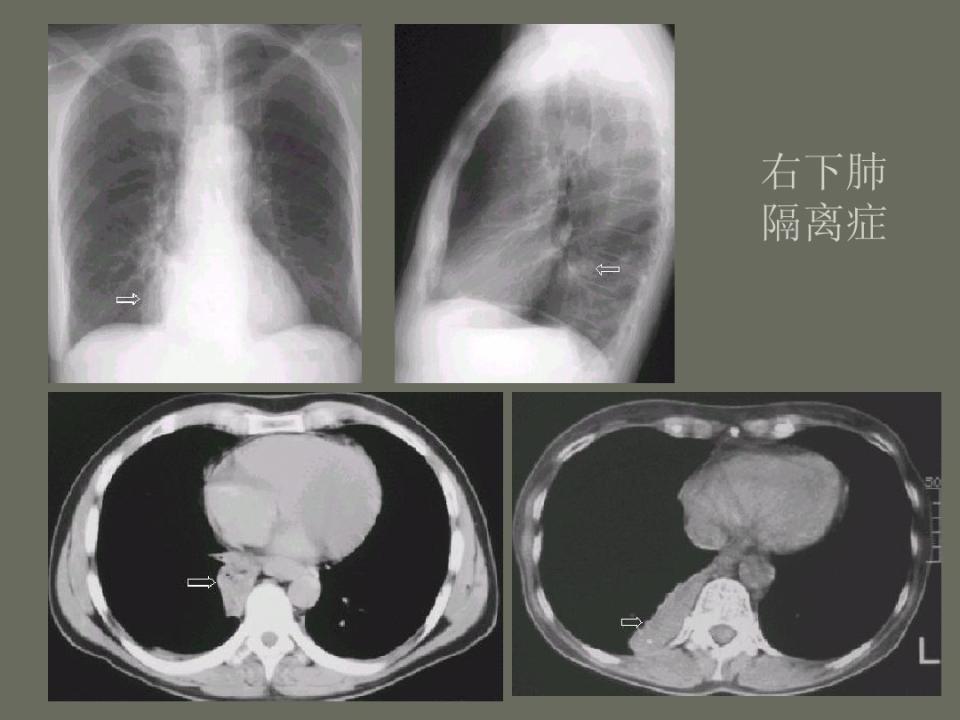

肺部先天性疾病的影像诊断